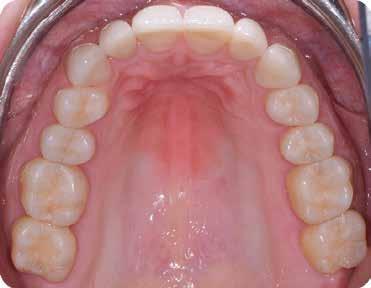

Eredmények: (3) és RAC-B összpontszám 2 (2-2-2/ 2) az 1 éves CBCT-követéskor (30–32. ábra), (4, 5,). Az 1 éves követéskor a lágyrészeken nem volt látható recesszió, csak enyhe színkülönbség a sebgyógyulás és a keratinizált szövet között, de ez a páciens számára nem aggályos (28. ábra).